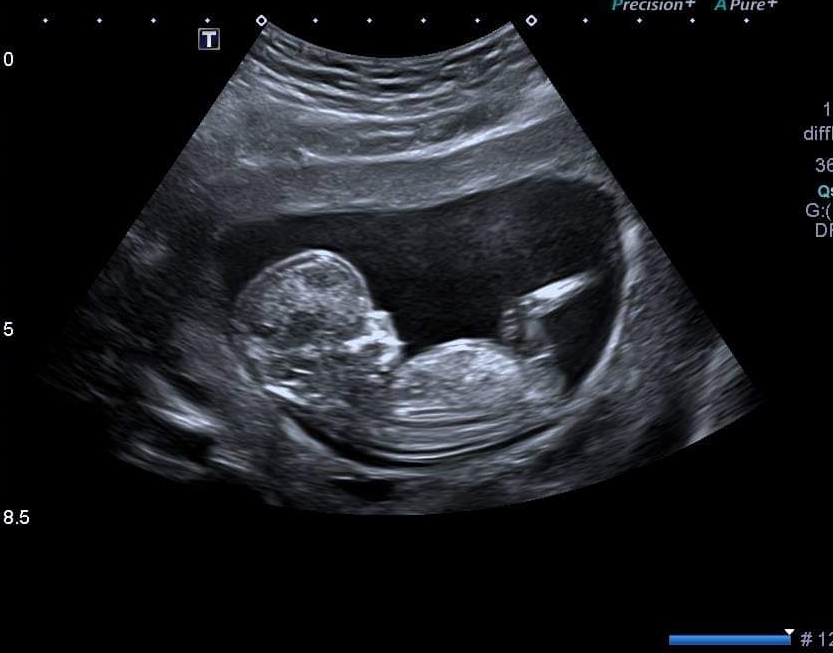

Would anyone be kind enough to guess the gender of my baby at 12+1? I'm not sure if there's a nub but I've included 3 pics so hopefully there's some clues.

Possibly a boy as there looks to be some stacking on picture 1. I’m not great at nun theory though. Picture 3 alone looks more girly as can’t see the stacking but I’m leaning blue